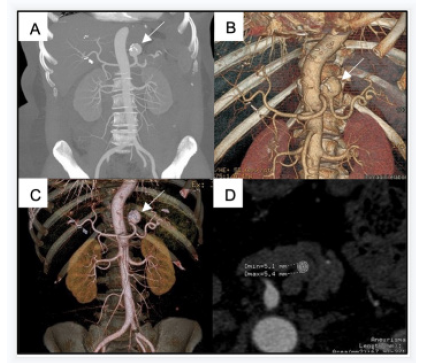

We present the case of a 57-year-old man who complained of upper left abdominal pain for 6 months. A CT angiography showed a 5 cm splenic artery aneurysm (Figure 1). His past medical history was not significant, and he had no significant comorbidities.

Figure 1: Preoperative CT angiography. MIP (A) and 3D reconstructions (B and C) show a 5 cm splenic artery aneurysm (arrows). The diameter of the splenic artery is 5 mm (D).